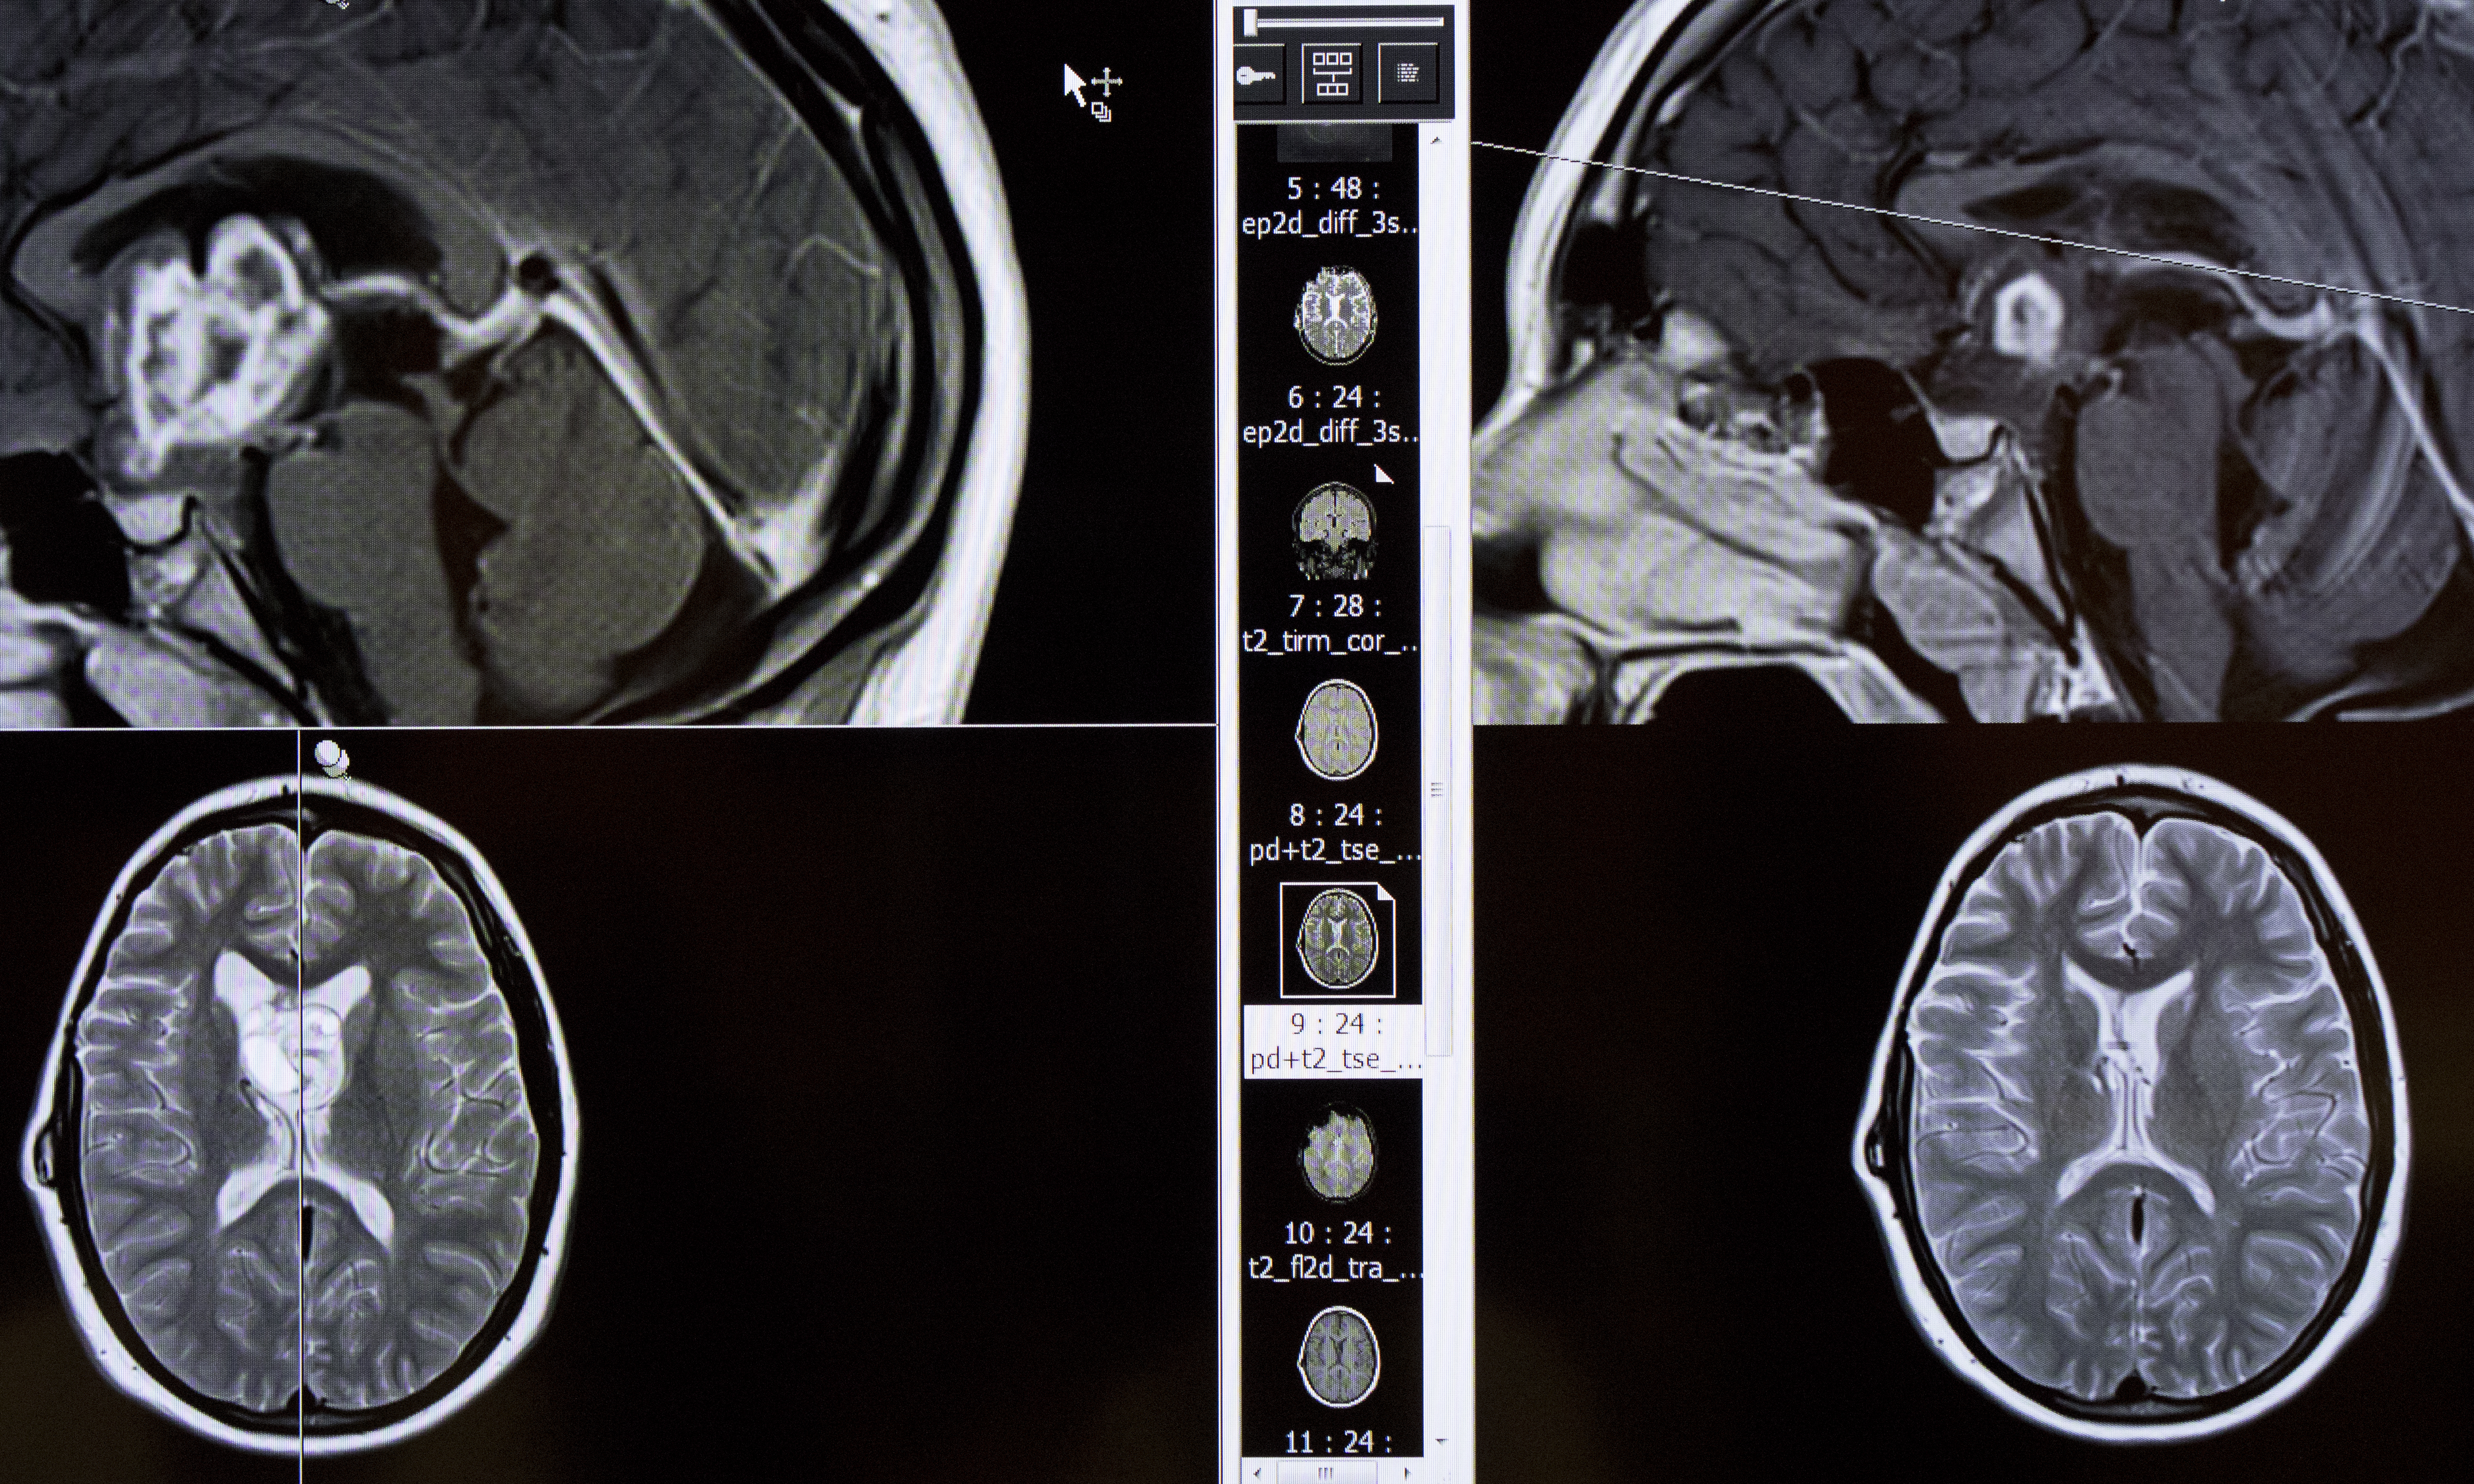

Nazemi begins the discussion, going over concerns for each patient as neuroradiologist Jim Anderson, M.D., displays MRI scans of the patient’s brain or spine on two large screens. If a biopsy or tumor removal has been done, a neuropathologist shows slides of the cells under a microscope, indicating the tumor’s type and how aggressive it might be.

Once a week the Pediatric Brain Tumor Board group meets at OHSU to review the cases of children with brain tumors. The group is comprised of specialists from different disciplines, working together to help give each child the best possible outcome. (OHSU/Kristyna Wentz-Graff)